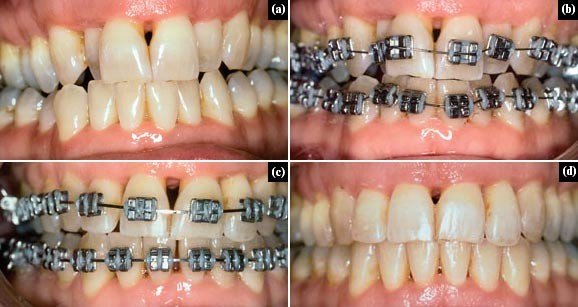

Metal Braces

Traditional and highly effective braces made of durable stainless steel. They are reliable for correcting complex alignment issues.

Ceramic Braces

Tooth-colored braces that blend with your natural teeth, offering a more aesthetic alternative to metal braces.